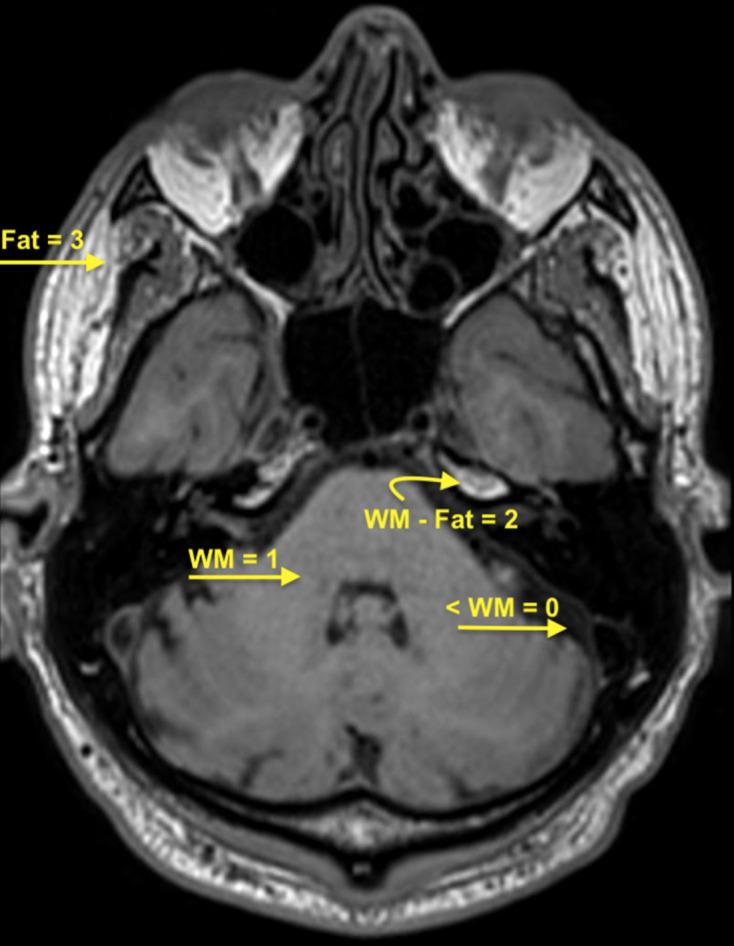

Enhancement patterns of the normal facial nerve on three-dimensional T1W fast spin echo MRI.

Pre- and post-gadolinium 3D T1W fast spin echo imaging studies ( = 64) were retrospectively analysed in patients without suspected facial nerve pathology. Two independent observers scored the signal at each of six skull base facial nerve segments. Wilcoxon signed-rank test was used to compare changes in signal between pre- and post-gadolinium sequences at each location, and how this differed between proprietary sequences or between the pairs of facial nerves.

There was significant enhancement at the fundal canalicular (16%), geniculate ganglion (96%), tympanic (45%) and mastoid (38%) facial nerve segments ( < 0.05). Two different proprietary sequences demonstrated similar patterns of enhancement and there was symmetry between the two sides.